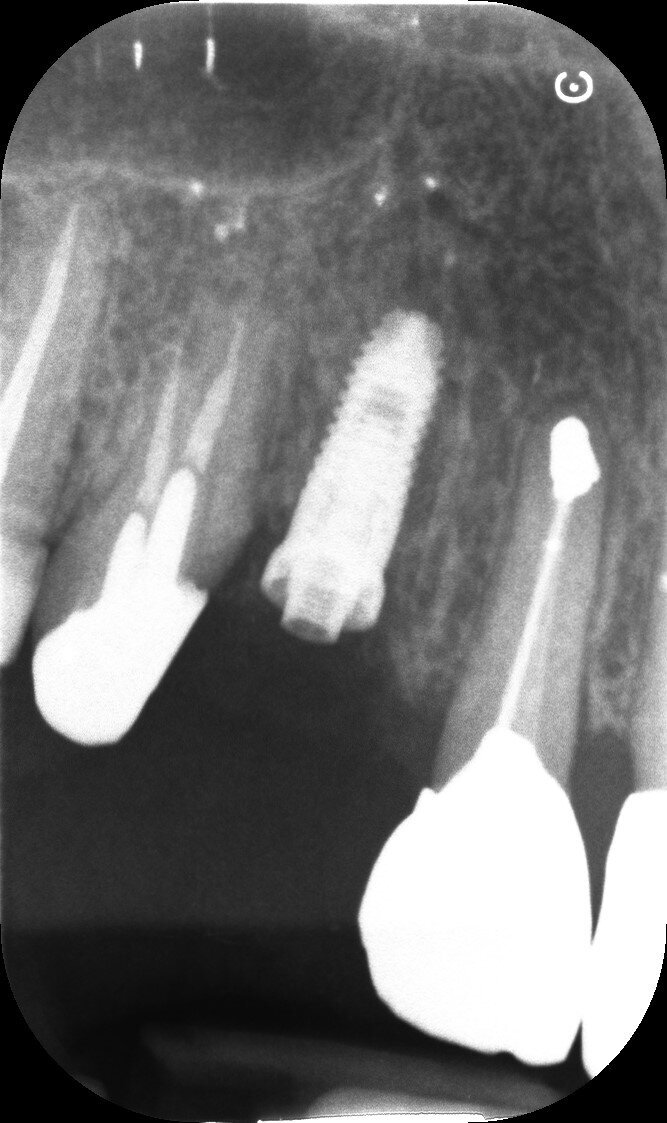

Il dente all’osservazione clinica e radiografica appare devitalizzato e ricostruito per mezzo di una perno moncone fuso e una corona in metallo ceramica collegata ad una corona sul dente 1.4 (Figg. 1, 2). All’esame parodontale si rileva un sondaggio puntiforme in zona palatale che indica la presenza di una frattura radicolare (Fig. 3). La paziente riporta una precedente apicectomia a carico del dente 1.2, come si evince dall’esame come-beam che ne evidenzia gli esiti a carico dell’osso apicale all’elemento 13 (Fig. 4).